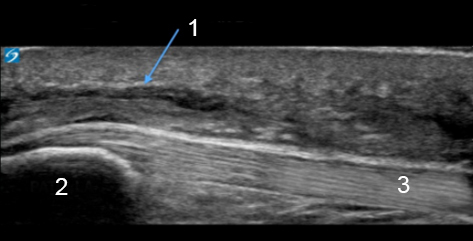

Knee Pre-Patellar Bursitis Image

Pre-Patellar Bursitis

Patella

Patellar Tendon